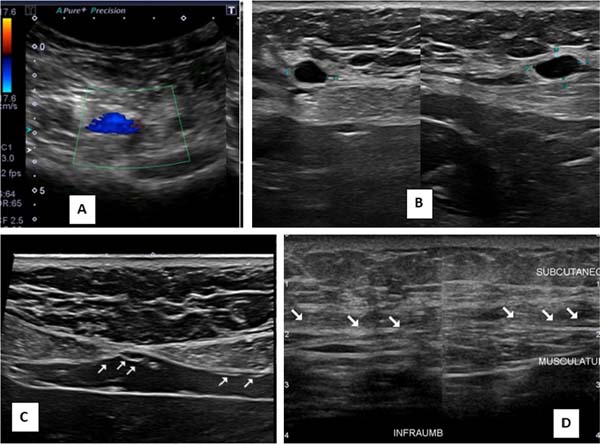

Ultrasounds carried out at different periods did not allow any identification of the implanted membranes, even early on. In the first 30 days after surgery, small, scattered seromas could be observed in the area of the implants, with no clinical relevance, disappearing after this period. No long-term local recurrences were observed, nor were there any anatomical changes in the operated region (Figures 2A-D).

No aspiration drains were used in any of the cases in this series, and in only one case, there was a need for aspiration puncture to treat a small seroma. Ultrasounds performed at different postoperative periods show small, scattered seromas present in the first 30 days, not being observed in late cases, with a normal-looking subcutaneous/aponeurosis interface without visualization of the membranes.